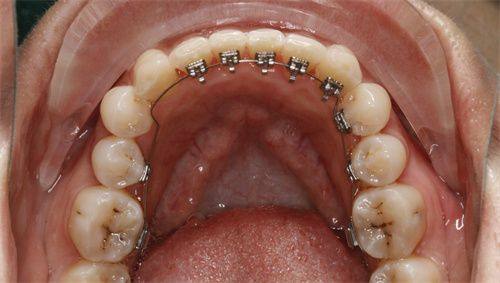

不过,成人整牙和青少年整牙还是有一些区别的。成人的牙齿和颌骨已经基本发育完成,矫正的难度和风险相对较大,治疗周期也会更长。而且,为了保持矫正成效,成人需要佩戴更长时间的保持器。

成人整牙面临着一些挑战。首先,牙齿移动速度相对较慢,这就意味着矫正周期会延长。其次,成人可能存在一些口腔问题,如牙周炎、龋齿等,需要在矫正前进行治疗,以确保矫正的顺利进行。

但成人整牙也有自己的优势。成人具有更强的自律性,能够更好地配合医生的治疗,按时佩戴矫治器和保持器。而且,成人对美的追求更加明确,矫正的动力也更足。